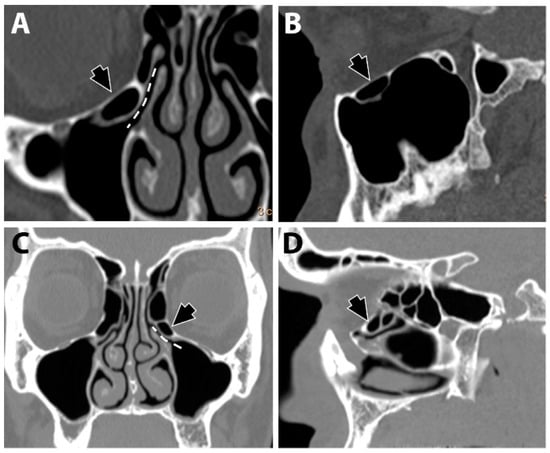

2.3. Evaluating the Maxillary Sinus Volume

The DICOM files’ stack of each scan was imported to Amira software (v. 6.3). The maxillary sinus surfaces (Figure 3) were virtually extracted using semi-automatic and automatic tools. First, to determine the boundaries of the sinuses, the skull was segmented using a threshold tool with masking adjusted to the bone density. Then, in each sinus space, the first, middle, and last slices were marked with the brush tool and interpolated for all slices. Lastly, the sinus surfaces were automatically created using the watershed tool and a gradient image. Unrelated parts (such as the infundibulum) were cleaned from the surface using the lasso tool. The left and right maxillary sinus volumes (L-MSV and R-MSV) were automatically calculated (in cube millimeters) from each sinus surface, using the ‘Surface Area Volume’. An average sinus volume variable was calculated using (RMSV + LMSV)/2.

Figure 3.

The right and left maxillary sinuses were segmented using Amira software (v. 6.3) using automated and semi-automated techniques. Using the brush and the interpolation tools, each sinus was marked on the axial (A), sagittal (B), and coronal (C) views and then a surface was generated from the 3D segmentation model (D). The volume (mm3) of each sinus was calculated from the surface using the ‘Surface Area Volume’ module.

The maxillary sinus volume was divided into three groups, as follows: “Small”: volume < 12 cm3, “Medium”: volume > 12 cm3, and <16 cm3, and “Large”: volume > 16 cm3.